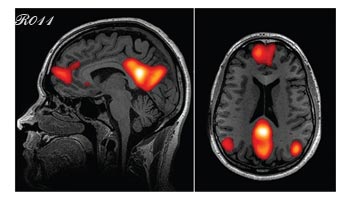

C’est ainsi qu’une étude publiée en 2024 par le MIT a pu montrer que l’utilisation de ChatGPT pour résoudre un problème complexe se traduit par une réduction de l’activité du cortex préfrontal dorso-latéral qui est associé à la planification et la prise de décision.

Cortex préfrontal dorso-latéral.

Parallèlement, le réseau du mode par défaut, (celui de la rêverie et de la pensée associative) est davantage activé

Réseau du mode par défaut.